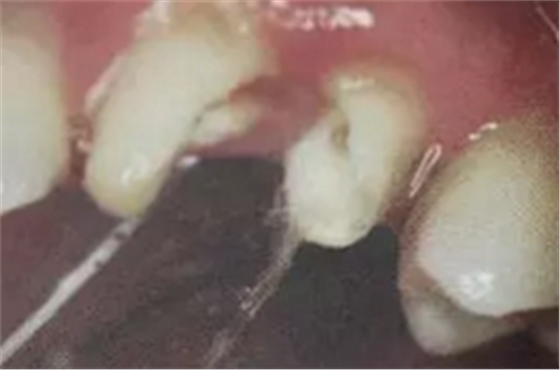

6. 纖維樁的試放和裁戴

纖維樁試放時(shí)應(yīng)用鑷子夾持將其插入預(yù)備的根管樁道中(這涉及無菌觀念和操作),就位時(shí)無阻力可稍有錮住感。

(鑷子夾持(正確))

(污染手套夾持(錯(cuò)誤))

(技工鉗裁剪(錯(cuò)誤))

試放后應(yīng)按所需長度用細(xì)粒金剛砂車針切割裁剪。

(粘樁堆核固化后裁剪)

為防止裁剪過程中有可能造成樁表面的污染,可以粘結(jié)固位后再進(jìn)行裁剪。

操作時(shí)。光固化燈應(yīng)在樹脂核成形后,頰、舌、合面分別光照20秒,在完成預(yù)備體后將其磨除。